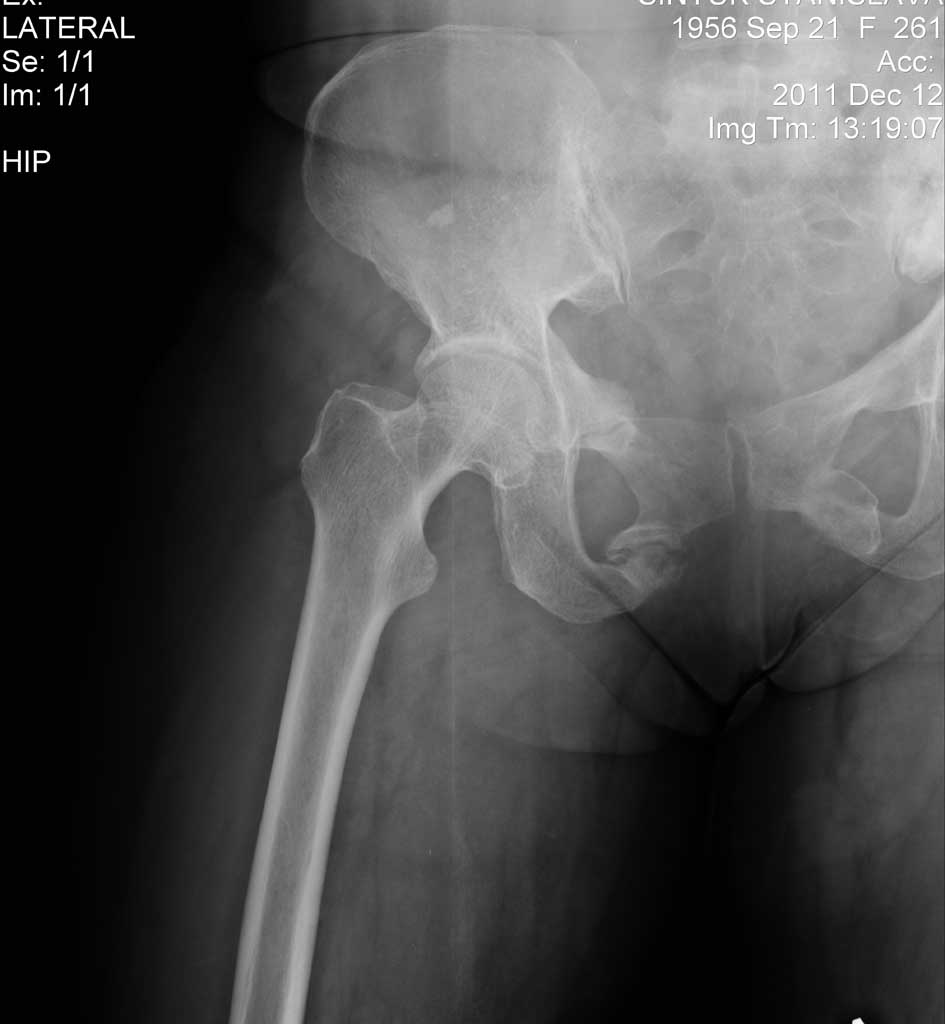

Добрый день. Есть вопрос относительно тактики лечения, синтеза(доступа, фиксатора).

Травма 3 года назад , перелом типа "бабочки".В настоящее время беспокоят боли в области

лонной кости при стоянии и ходьбе, в покое все спокойно.